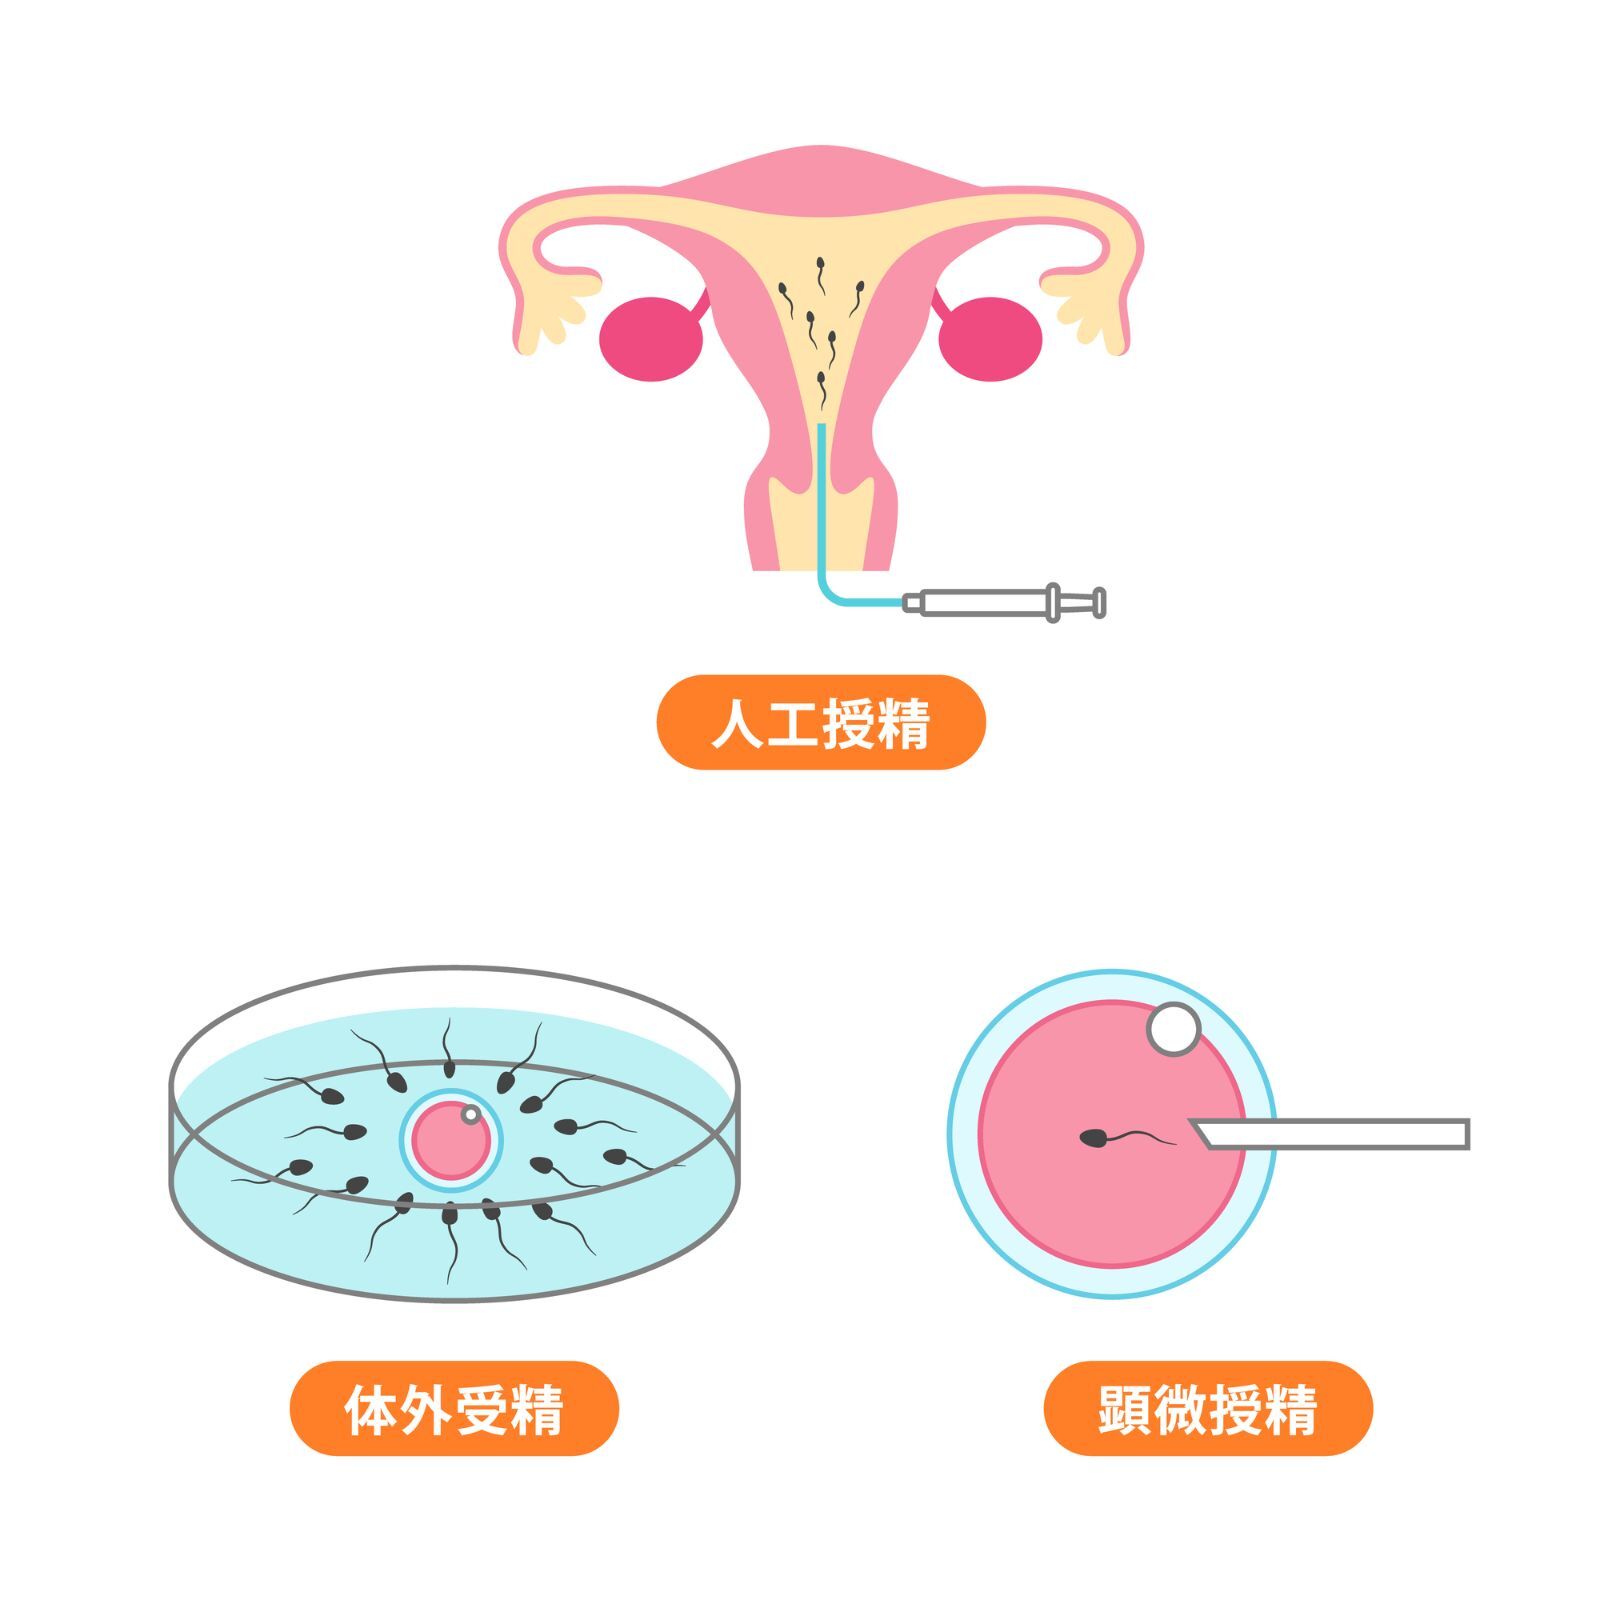

不妊治療と並行してCHONPSの食事管理を始めました。特に良質な脂質とミネラルバランスを意識した食事に変えたことで、卵子の質が向上したと先生に言われ驚きました。無事妊娠でき、今は双子の男の子のママに!食事の大切さを実感する毎日です。CHONPSに出会えて本当に良かった。